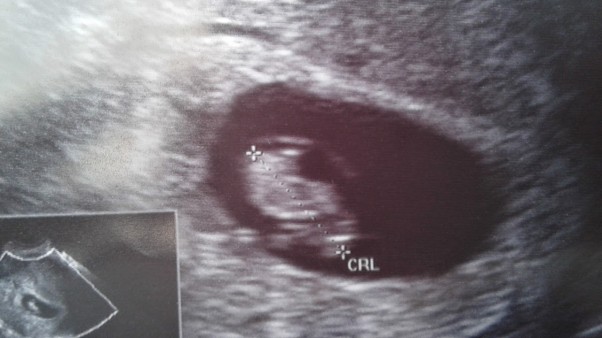

Pierwsze USG - 17 czerwca - i jest! Nasza mała fasolka!